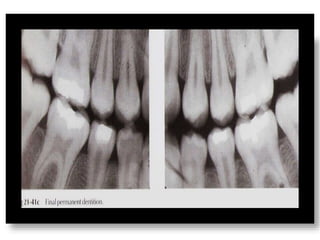

Distal Shoe

• Should be evaluated with

radiograph prior to

cementation

– Length

– Position

• Will be replaced with

another space maintainer

when permanent teeth

erupt.

Distal Shoe • Shouldbe evaluated with radiograph prior to cementation – Length – Position • Will be replaced with another space maintainer when permanent teeth erupt.